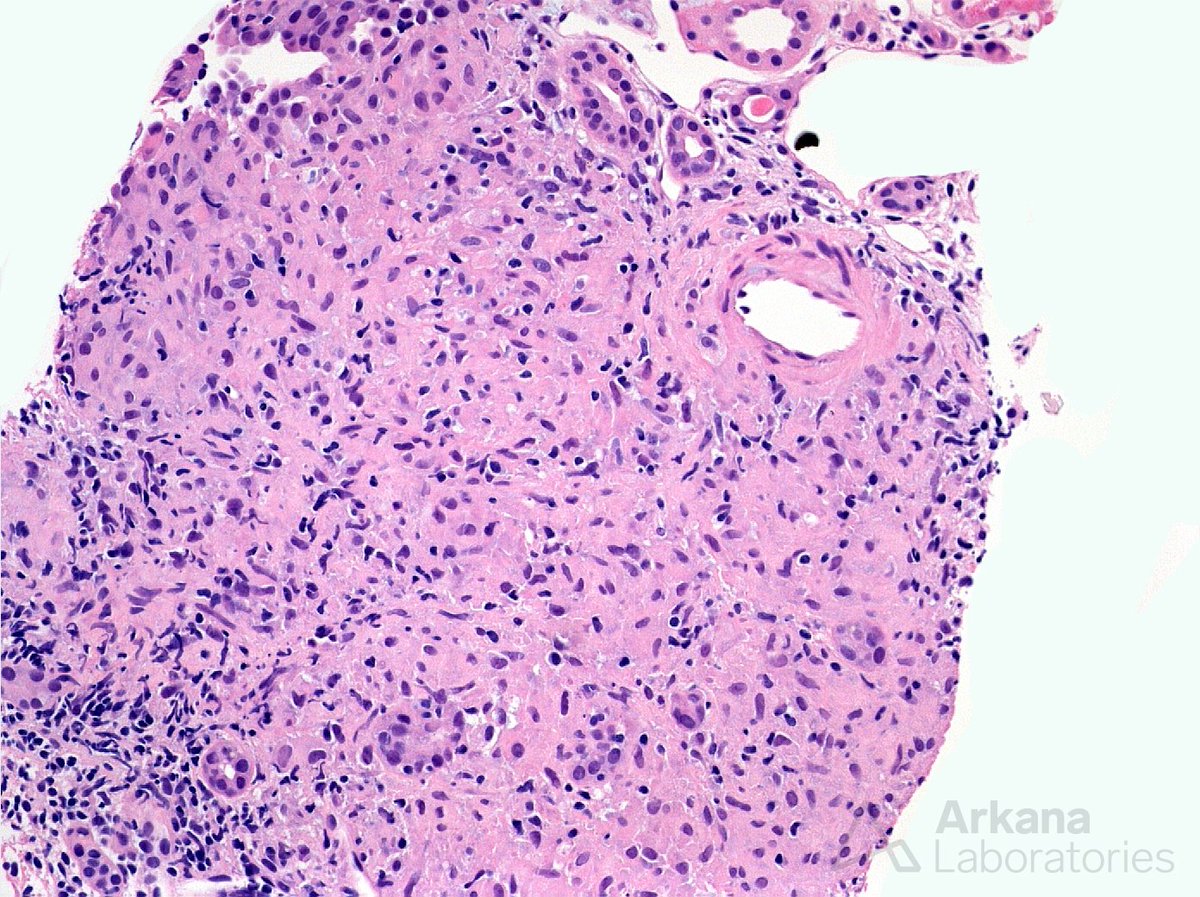

#TeachingPoints A 75 year old woman presented for her annual checkup with no complaints. She had a past medical history of hypertension and her blood pressure at this visit was 160/80. Laboratory findings were significant for an elevated serum creatinine at 2.1 mg/dL (baseline 1.0 mg/dL) as well as proteinuria of 855 mg/24 hr. All serologies, including proteinase-3, myeloperoxidase, and anti-nuclear antibodies were negative. A kidney biopsy was performed to evaluate the decreased kidney function and proteinuria. It revealed a total of five glomeruli were present, three of which showed a global endocapillary proliferation of large atypical cells with frequent mitotic figures (Photomicrographs A and B). These atypical cells were isolated to the glomeruli and stained positive for CD20 . The remaining glomeruli did not contain any proliferative changes. Electron microscopy and immunofluorescence were both negative for immune deposits. This is a rare subtype of extranodal diffuse large B cell lymphoma that has been known in the past by several different names and was originally thought to be a proliferation of endothelial cells; however, it is currently classified by the WHO as “intravascular large B-cell lymphoma” (IVBCL). IVLBCL most frequently affects adults over 60 and is typically widely disseminated in the small vessels of many organs at presentation. It most often presents without tumor masses or lymphadenopathy and lymphoma cells are usually not seen in peripheral blood smears. Clinical symptoms are highly variable and usually result from the occlusion of small vessels. The vast majority of cases are diagnosed in the bone marrow, liver, spleen, or skin. However, there are case reports of the diagnosis being made by kidney biopsy. In these cases, it usually manifests with slowly progressive renal failure and proteinuria which is frequently in the nephrotic range. #RenalPath